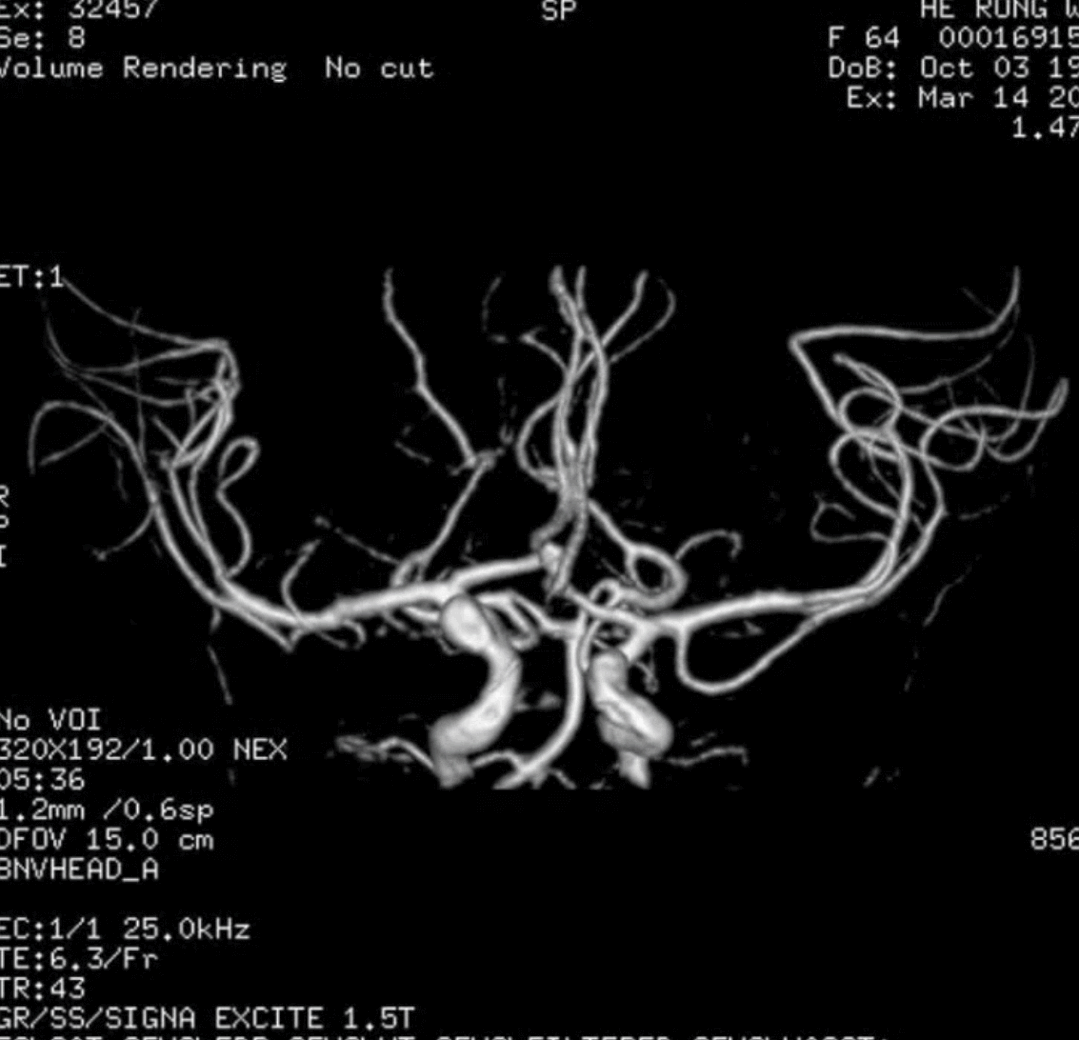

🔆  行头MRI+MRA示:脑内散在小缺血灶;老年性脑萎缩;双侧颈内动脉床突上段动脉瘤

MRI+MRA

右侧颈动脉造影

左侧颈动脉造影

左侧瘤体形态欠规则,4mm×30mm Streamline 优先处理左侧动脉瘤

术后3月复查,瘤体未见显影,载瘤动脉通畅

同期4mm×20mm Streamline 进一步处理右侧动脉瘤